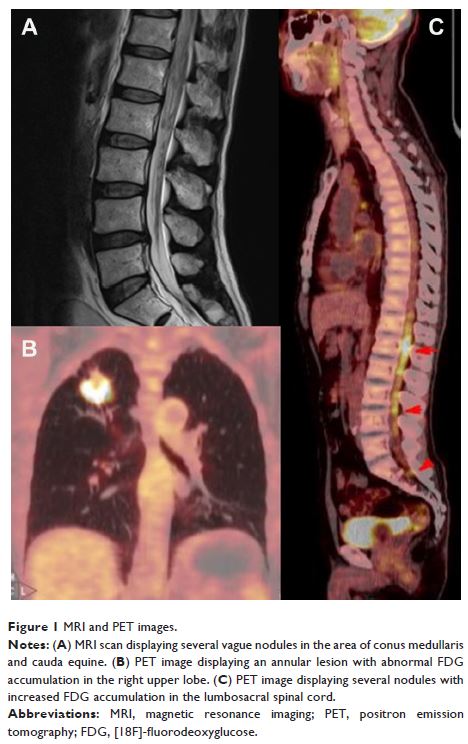

首发为马尾综合征的肺癌软脑膜转移:病例报告及文献复习